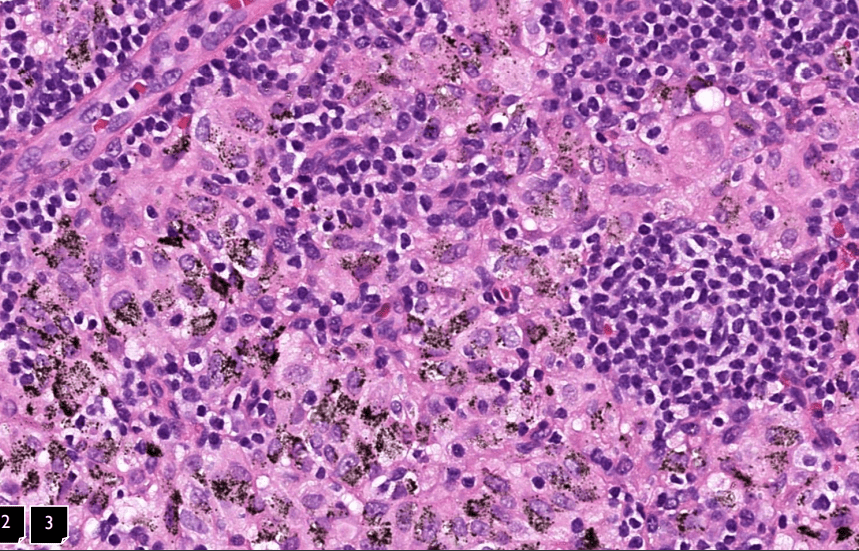

Pathology Micro-2

Tumor Description:

1. border(infiltrative到哪裡/circumscribed/capsule)

2. architecture

3. cell 長相

4. stroma

5. 其他周邊異常

5. stromal desmoplasia

(apoptosis/prominent nucleoli)

(melanin pigment)

(circumscribed/infiltrative)